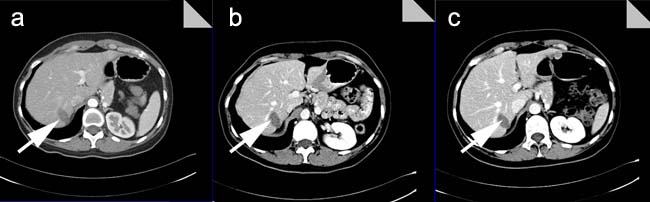

After three days of MWA treatment, all patients in this trial were subjected to the contrast-enhanced ultrasound in order to identify the inactivated status of the liver tumor, with which we can determine whether other potential treatments were necessary. Following the identification of ultrasound, alterations in patient pain grade, bogy temperature, detection of routine blood and liver function tests were further identified. And then the patients were examined using enhanced CT/MRI or ultrasound imaging every 3 months following our therapy (Figure 3).

Figure 3: Post-operative CT imaging in a cohort of MWA patients. a. After one month post-treatment with MWA, the CT imaging showed the low intensity of lesions without peripheral enhancement; b. After three months post-treatment with MWA, the CT imaging showed the low intensity of lesions without peripheral enhancement; c. After six months post-treatment with MWA, the CT imaging showed much lower intensity of lesions without peripheral enhancement than ever.